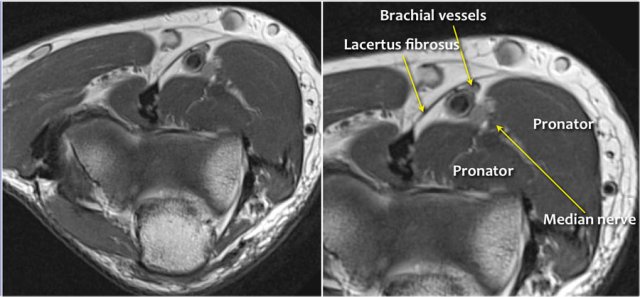

The median nerve goes down behind the Lacertus fibrosis, which is the aponeurosis of the biceps and penetrates the pronator muscle.